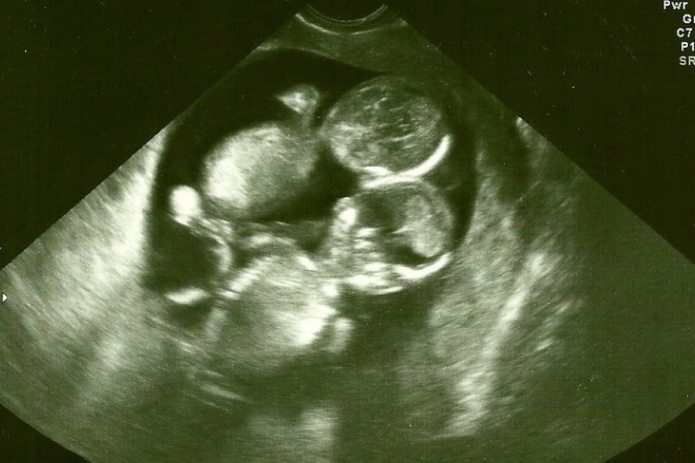

▼生产当天凯特跟家人都无比紧张,当医生剖开她的孕肚时,却看到了相当不可思议的场景:新生双胞胎的脐带紧紧缠绕着,就像一条错综的麻花辫!但它并没有阻碍宝宝摄取养分,两位小女婴都顺利生下来了!